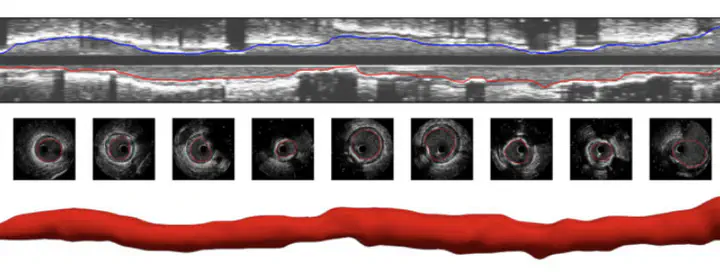

Automated lumen segmentation using multi-frame convolutional neural networks in intravascular ultrasound datasets

Aims: Assessment of minimum lumen areas in intravascular ultrasound (IVUS) pullbacks is time-consuming and demands adequately trained personnel. In this work, we introduce a novel and fully automated pipeline to segment the lumen boundary in IVUS datasets. Methods and results: First, an automated gating is applied to select end-diastolic frames and bypass saw-tooth artefacts. Second, within a machine learning (ML) environment, we automatically segment the lumen boundary using a multi-frame (MF) convolutional neural network (MFCNN). Finally, we use the theory of Gaussian processes (GPs) to regress the final lumen boundary. The dataset consisted of 85 IVUS pullbacks (52 patients). The dataset was partitioned at the pullback-level using 73 pullbacks for training (20 586 frames), 6 pullbacks for validation (1692 frames), and 6 for testing (1692 frames). The degree of overlapping, between the ground truth and ML contours, median (interquartile range, IQR) systematically increased from 0.896 (0.874–0.933) for MF1 to 0.925 (0.911–0.948) for MF11. The median (IQR) of the distance error was also reduced from 3.83 (2.94–4.98)% for MF1 to 3.02 (2.25–3.95)% for MF11-GP. The corresponding median (IQR) in the lumen area error remained between 5.49 (2.50–10.50)% for MF1 and 5.12 (2.15–9.00)% for MF11-GP. The dispersion in the relative distance and area errors consistently decreased as we increased the number of frames, and also when the GP regressor was coupled to the MFCNN output. Conclusion: These results demonstrate that the proposed ML approach is suitable to effectively segment the lumen boundary in IVUS scans, reducing the burden of costly and time-consuming manual delineation.